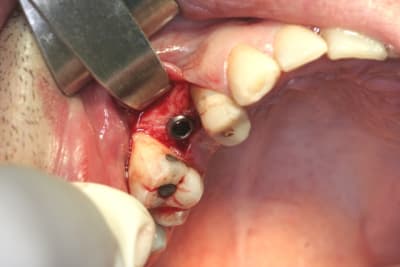

tiens...un ptit cas...

dans ce petit cas...j'ai commencé avec le kit MIS...et fini ma voie crestale avec le kit HBS...

ok, c'est un mini soulevé...mais bon , c'est un exemple...

juste une précision...premier foret 1.3mm sur 8mm...expansion pour mettre un implant de 4x10...

j'ai juste "léché" la préparation du site final avec le foret terminal du système...sur 8mm...avant d'insérer l'implant...stab primaire au top...blocage à 40 Ncm...

Céramik, c'est pas moi qui fais les photos pendant la chir...mais mon assistante...enfin une des 2 dans la salle de chir, celle qui est en non stérile...

je suis obligé, car c'est pas une pro de la photo, de lui simplifier la vie...et donc de faire des compromis sur les paramètres de prise de vue...je règle donc l'appareil en mode priorité au diaphragme (Av) avec une ouverture un peu passe partout (f22) et en 400 ISO...maintenant, le 100 équivaut à un 160mm en 24x36...et faut vraiment faire attention au flous de bougé...elle s'en est vite rendue compte...mais elle apprend vite et finalement c'est pas si mal, non???